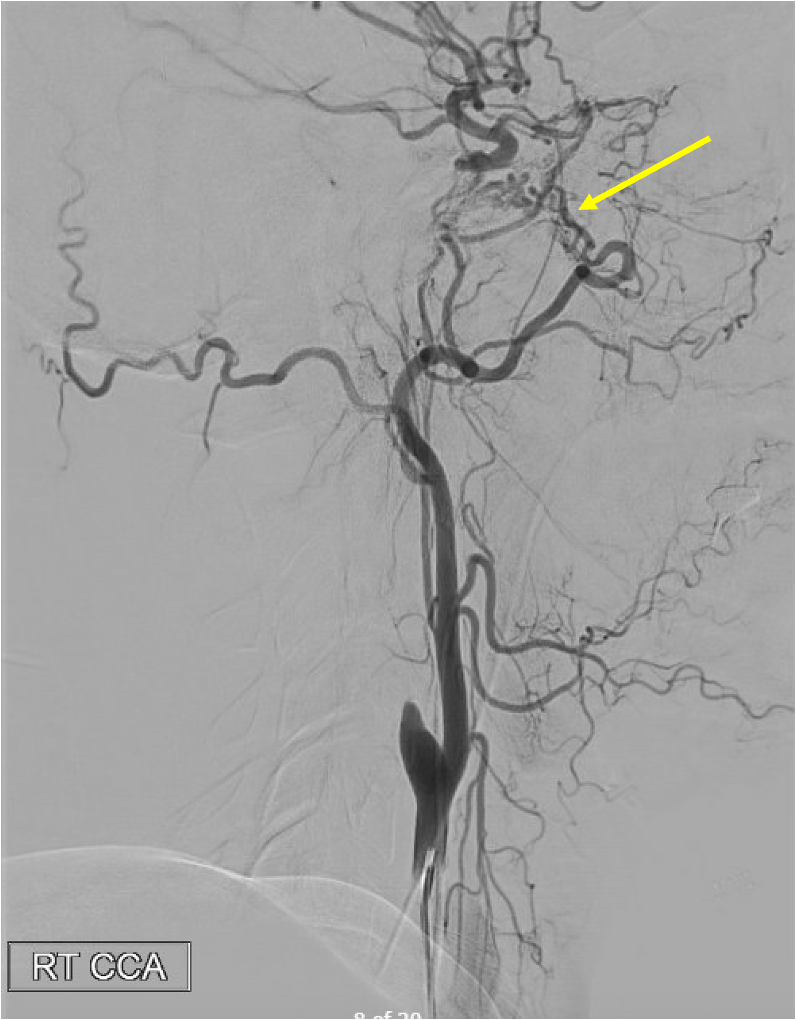

Pathologic early filling of this structure is seen on this AP view of the R CCA injection:

Cavernous sinus